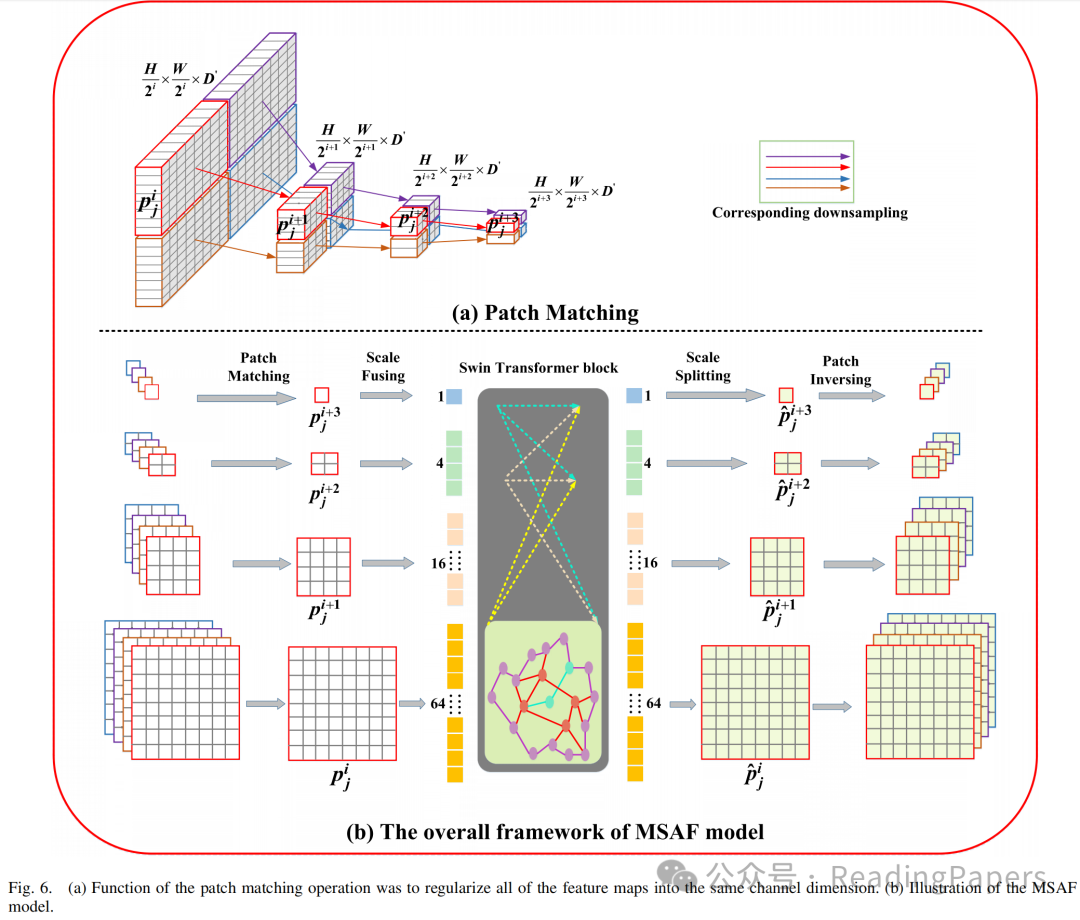

C. MSAF模型

已经证明,多尺度信号在分割具有复杂位置和大小变化的器官时极为有价值。为了解决多尺度特征之间的语义信息交互问题,作者利用了MSAF模块。该模块包括四个步骤:图像块匹配、尺度融合、尺度分割和图像块反转,这些步骤共同实现了跨尺度依赖关系的建立。MSAF模块的网络结构如图6所示。

具体来说,作者首先将所有特征图正则化到相同的通道维度,并通过下采样操作将它们分配到具有相同颜色的边界框中(即红色)。如果被视为第个尺度上的第个图像块,那么、和将是匹配的下采样图像块。通过这一步骤,作者能够在从第到第个尺度的四个连续特征映射上定位相关的空间感知图像块,保留最相关图像块的空间对应关系。

然后,作者通过尺度融合方法聚合不同尺度上的空间相关图像块,生成一系列标记。该过程可以描述为:

其中,表示拼接操作。由于这一系列标记缺乏2D空间信息,作者利用Transformer块来确保其空间结构的一致性。